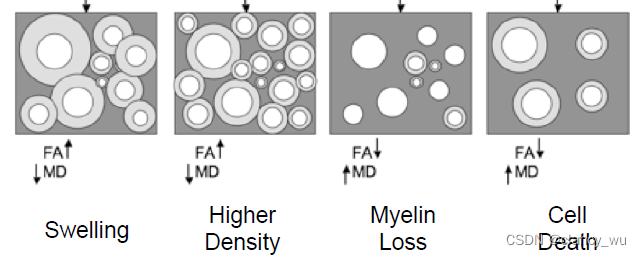

由此,可以得出各向异性的表达公式。各向异性的全称其实是Fractional Anisotropy,FA值,在[0, 1]之间。MD是平均扩散率

如下图:

不同场景对FA,MD的影响

细胞肿胀:

F

A

↑

,

M

D

↓

FA\uparrow,MD\downarrow

FA↑,MD↓

髓鞘丢失:

F

A

↓

,

M

D

↑

FA\downarrow,MD\uparrow

FA↓,MD↑

细胞死亡:

F

A

↓

,

M

D

↑

FA\downarrow,MD\uparrow

FA↓,MD↑

这个也很好理解,结合上述原理就能理解。值得注意的是,FSL特别强调,这只是可能的几种解释情况,但是实际情况很复杂,所以不要过度解读。